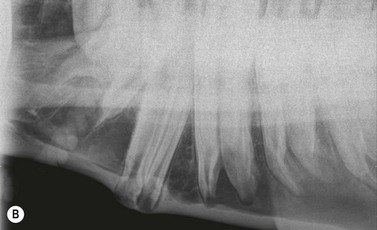

image

Fig. 8.9 (A) The supernumerary CT present at the caudal aspect of this maxillary CT row is overgrown due to absence of occlusal contact. Contact of the overgrowth with the caudal aspect of the lower 11 has caused it to displace caudally, causing a wide diastema (arrow) between it and the adjacent 11. (B) Intra-oral view of a supernumerary 212 that has overgrown and caused a diastema (arrow) to develop between it and the 211. The flat occlusal surface shows it has been reduced in the past.

In other instances where a caudal supernumerary tooth develops at the same time as the normal 11, overcrowding of the dental buds occurs prior to calcification. In these cases, the 11 and the supernumerary cheek tooth are both deformed and lie obliquely or possibly parallel to each other in separate or a common alveolus. Following eruption of the supernumerary cheek tooth, diastemata between these two distorted teeth allow food impaction also leading to painful periodontal disease. Unopposed caudal supernumerary CT will overgrow if not reduced (Fig. 8.11) and the overgrown teeth will become displaced caudally, causing diastema formation (Fig. 8.9).

In the rare cases where clinically significant diastemata do not occur adjacent to a supernumerary cheek tooth, continuing eruption of the unopposed supernumerary tooth causes an overgrowth (usually at the caudal aspect of the CT rows) (Figs 8.9 & 8.11). Consequently, it is very worthwhile in horses with caudal CT overgrowths, especially with unexplained development of such overgrowths, not to just assume that they are overgrowth of an 11, but to carefully count the teeth to assess if a supernumerary tooth is present. If any doubt exists, latero-oblique radiograph can confirm the presence of supernumerary teeth, but care must be taken not to mistake two overlapping teeth for a single, wide tooth. Very rarely, a second supernumerary tooth (e.g., Triadan 113) will develop caudal to the initial supernumerary cheek tooth as illustrated by Dixon et al.16